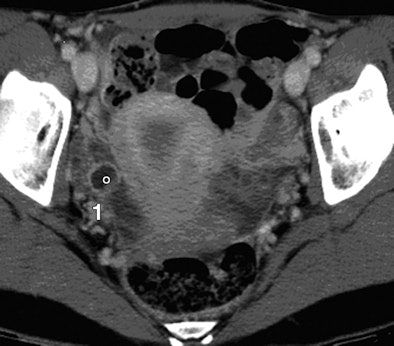

![]() |

| Thirty-four-year-old woman with normal endometrium. Axial contrast-enhanced CT image (above) shows prominent triangular-shaped endometrium. Number 1 and circle indicate incidental measure of ovarian cyst not relevant to endometrium or this article. Sagittal reconstruction image (below) of same patient shows normal thin endometrium on this magnified image. Images courtesy of the American Roentgen Ray Society; from Grossman J, Ricci Z, Rozenblit A, et al. Efficacy of contrast-enhanced CT in assessing the endometrium. AJR. 2008;191:664-669. |